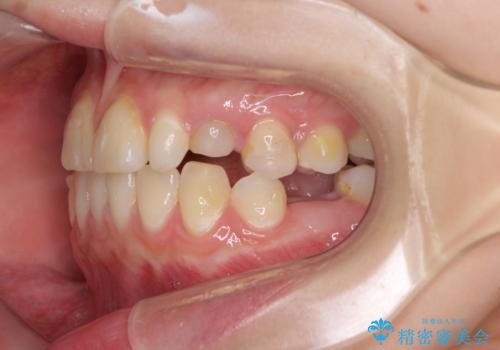

欠損と残存乳歯 矯正治療とインプラント治療

- 残存した乳歯や歯の欠損、歯並びを気にして来院された患者様です。

乳歯を残した状態は予後がよくないこと、矯正治療と補綴治療を総合的に進めていきたいとのことで、インビザラインによる矯正治療とインプラント補綴治療を並行して進めていくこととしました。

気になっていた部分がすべて解消され、患者様には大変満足していただきました。